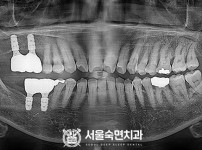

임플란트-전후사진1

임플란트-전후사진2

임플란트-전후사진3

임플란트-전후사진4